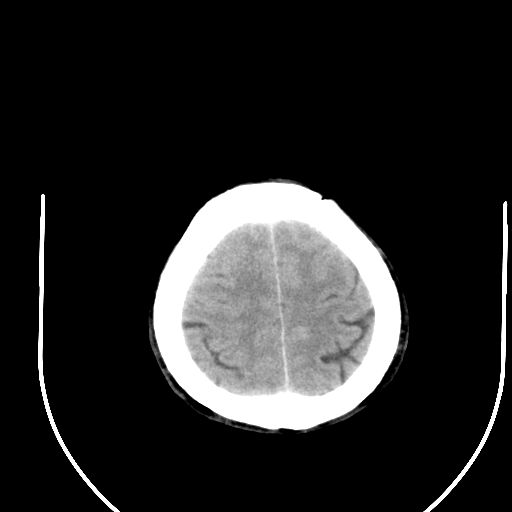

右侧基底节区脑出血并破溃入脑室。

1右侧基底节脑出血伴脑干出血并破入脑室系统脑疝形成2梗阻性脑积水

1)右侧基底节脑出血伴脑干出血并破入脑室系统。2)大脑镰下疝。3)梗阻性脑积水。

1、右侧基底节脑出血伴脑干出血并破入脑室系统。

2、大脑镰下疝。

3、梗阻性脑积水。